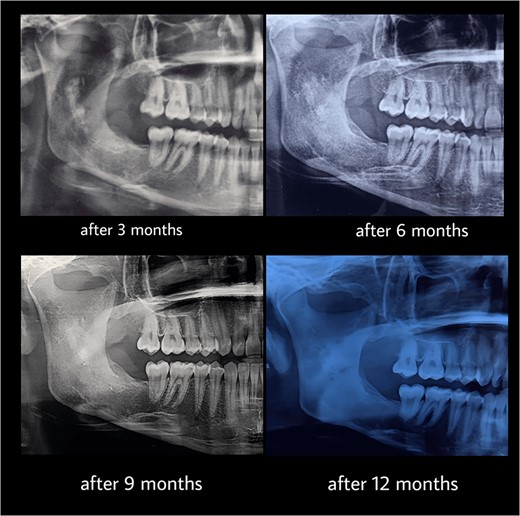

Under general anesthesia, an incision was made around the fistula to remove the overlying mucosa and expose the lesion. A 1 cm size window was made into the cyst cavity (Fig. 3). The cyst lining was sutured to surrounding mucosa. The cavity was kept open using a povidone iodine-saturated gauze, and it was replaced every 2 weeks. Follow-up radiograph (OPG) was recommended after 3, 6, 9 and 12 months (Figs 4 and 5).

Marsupialization procedure: exposure of the cystic cavity, 1 cm size window was made into the cyst cavity.